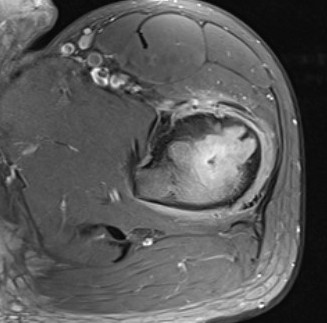

MRI

Lucent lesion with nidus or calcification

Spinal lesion

- bone expansion

- intralesional stippled ossification